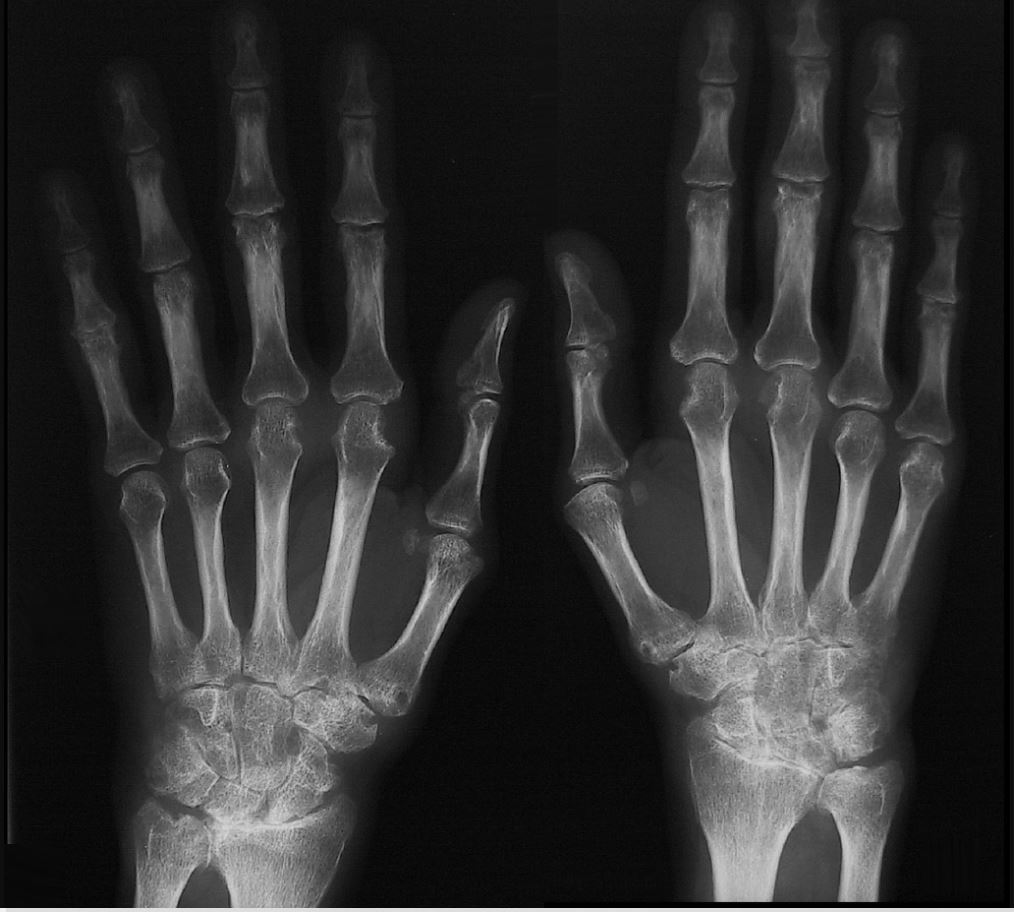

Rheumatoid Hand:

1. Describe features seen on this plain radiograph.

A

• bilateral and symmetrical involvement

• proximal interphalangeal & metacarpophalangealjoint space narrowing

• metacarpal heads erosions

• metacarpophalangeal joint osteopenia

• pancarpal and radiocarpal involvement with erosions

• carpometacarpal erosion

• distal radioulnar joint loss of space

• distal interphalangeal joints spared

• soft tissue swelling